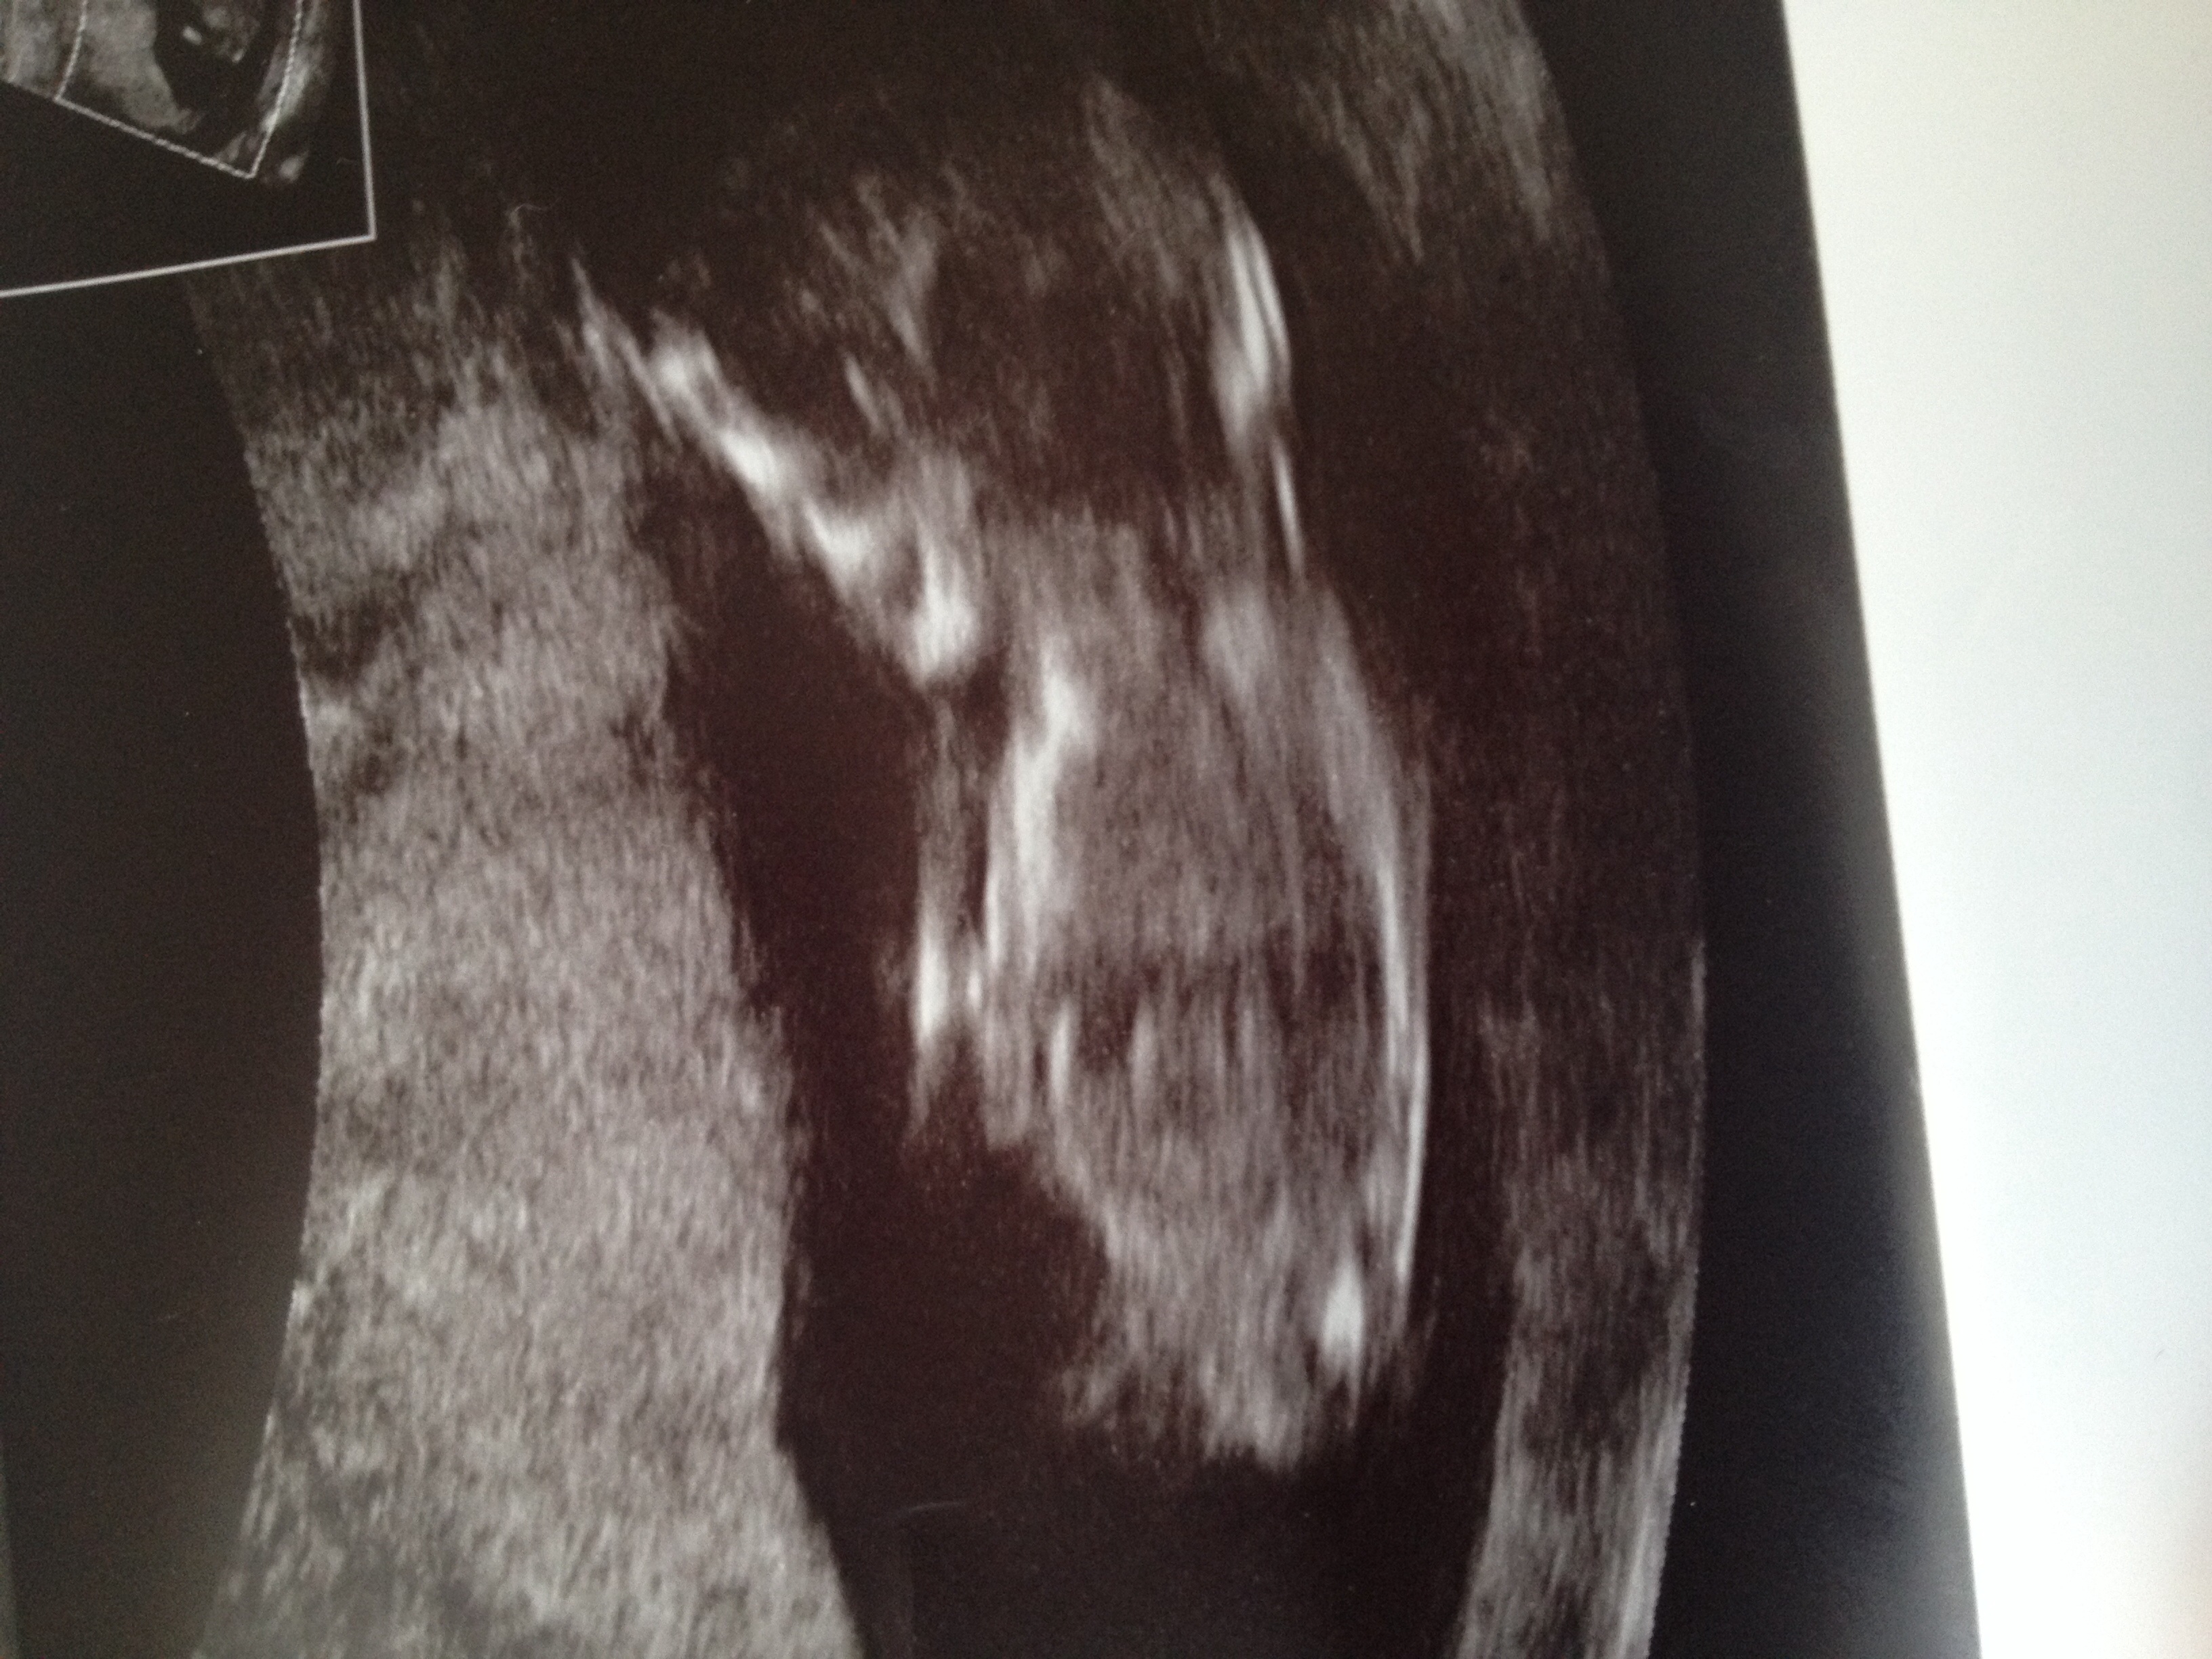

13+1. Does Antoine see the nub? Boy or girl?